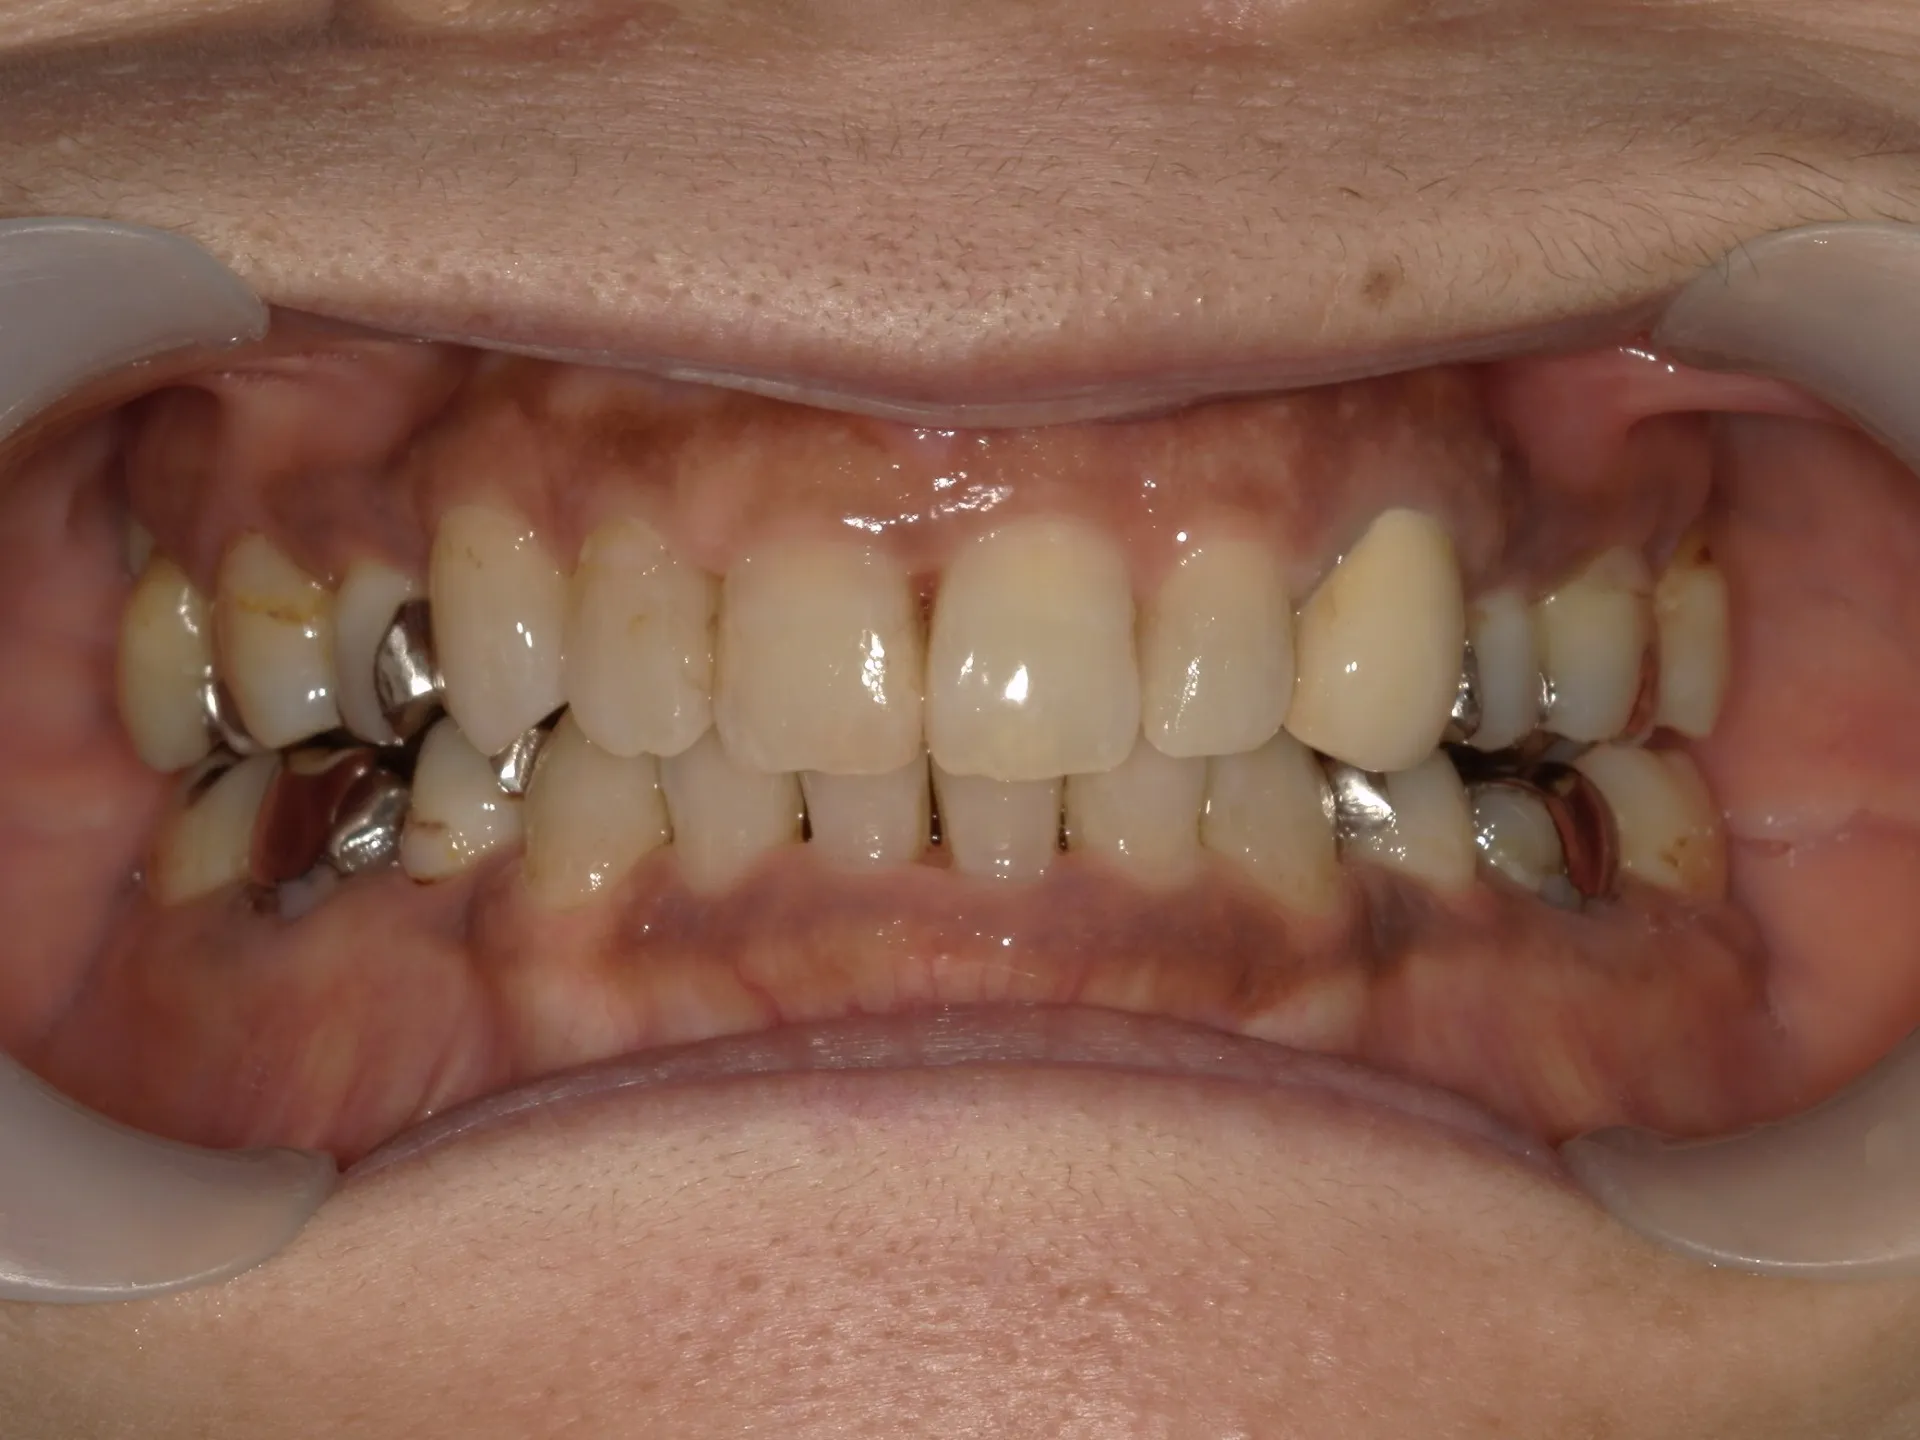

今回は65歳以上でも矯正治療を開始した症例についてご紹介いたします。

しかし、年齢がたとえ定年を迎えたあとであっても十分に矯正が行えて、今後の歯磨きが容易になり、虫歯や歯周病のリスクが減らせて歯を残すことが出来たり、歯並びが良くなったことでモチベーションも上がるなどの矯正後のメリットも非常に高いため、健康的な生活を行う上でも矯正治療は行うことをお勧めします。